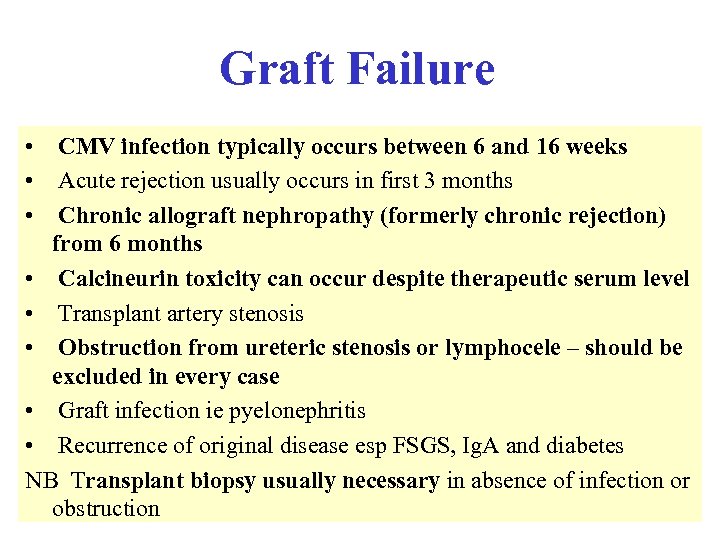

Graft Failure • CMV infection typically occurs between 6 and 16 weeks • Acute rejection usually occurs in first 3 months • Chronic allograft nephropathy (formerly chronic rejection) from 6 months • Calcineurin toxicity can occur despite therapeutic serum level • Transplant artery stenosis • Obstruction from ureteric stenosis or lymphocele – should be excluded in every case • Graft infection ie pyelonephritis • Recurrence of original disease esp FSGS, Ig. A and diabetes NB Transplant biopsy usually necessary in absence of infection or obstruction

Graft Failure • CMV infection typically occurs between 6 and 16 weeks • Acute rejection usually occurs in first 3 months • Chronic allograft nephropathy (formerly chronic rejection) from 6 months • Calcineurin toxicity can occur despite therapeutic serum level • Transplant artery stenosis • Obstruction from ureteric stenosis or lymphocele – should be excluded in every case • Graft infection ie pyelonephritis • Recurrence of original disease esp FSGS, Ig. A and diabetes NB Transplant biopsy usually necessary in absence of infection or obstruction